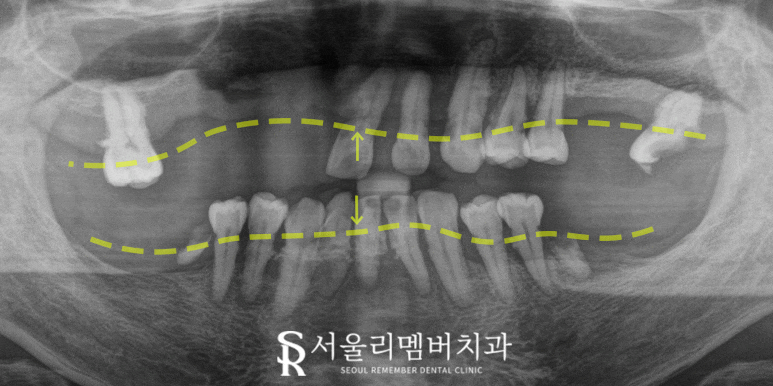

한눈에 봐도 상태가 많이 심각해 보입니다.

치주염으로 잇몸이 내려앉아

치근이 거의 드러난 곳도 관찰할 수 있었습니다.

전체적으로 잇몸 부종도 있고

깨진 치아도 발견되었습니다.

아랫니에서는 치근만 남은 것과

치석이 많이 쌓여져 있네요.

더 자세한 확인을 위해

x-ray 촬영을 진행한 결과,

치조골이 많이 퇴축된 모습이었고

치아를 살린다 하더라도 얼마 못가

부러질 가능성이 현저히 높았습니다.